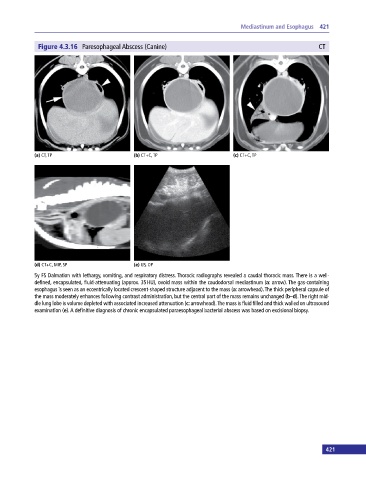

Figure 4.3.16 Paresophageal Abscess (Canine) CT

(a) CT, TP (b) CT+C, TP (c) CT+C, TP

(d) CT+C, MIP, SP (e) US, OP

5y FS Dalmation with lethargy, vomiting, and respiratory distress. Thoracic radiographs revealed a caudal thoracic mass. There is a well‐

defined, encapsulated, fluid‐attenuating (approx. 35 HU), ovoid mass within the caudodorsal mediastinum (a: arrow). The gas‐containing

esophagus is seen as an eccentrically located crescent‐shaped structure adjacent to the mass (a: arrowhead). The thick peripheral capsule of

the mass moderately enhances following contrast administration, but the central part of the mass remains unchanged (b–d). The right mid

dle lung lobe is volume depleted with associated increased attenuation (c: arrowhead). The mass is fluid filled and thick walled on ultrasound

examination (e). A definitive diagnosis of chronic encapsulated paraesophageal bacterial abscess was based on excisional biopsy.